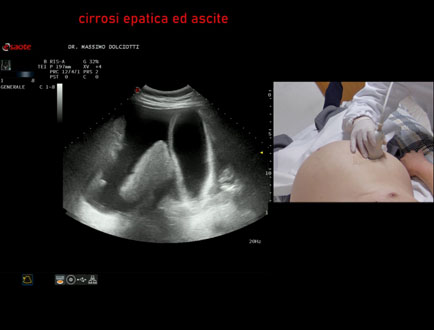

Data inserimento: 16/02/2024

Ecografia del: 14/02/2024

Strumento: Esaote MyLab Eight

Sonda: Convex Multifrequenza 1-8 MHz

Età Paziente: F 87 anni

Motivazione dell'esame: anemia severa, incremento del volume dell'addome.

Commento all'esame: le immagini ed il video documentano il fegato, ridotto di dimensione, ad ecostruttura disomogenea, di aspetto nodulare, a profilo irregolare, con presenza di ascite.

Conclusioni: cirrosi epatica scompensata con ascite (decompensated liver cirrhosis with ascites).